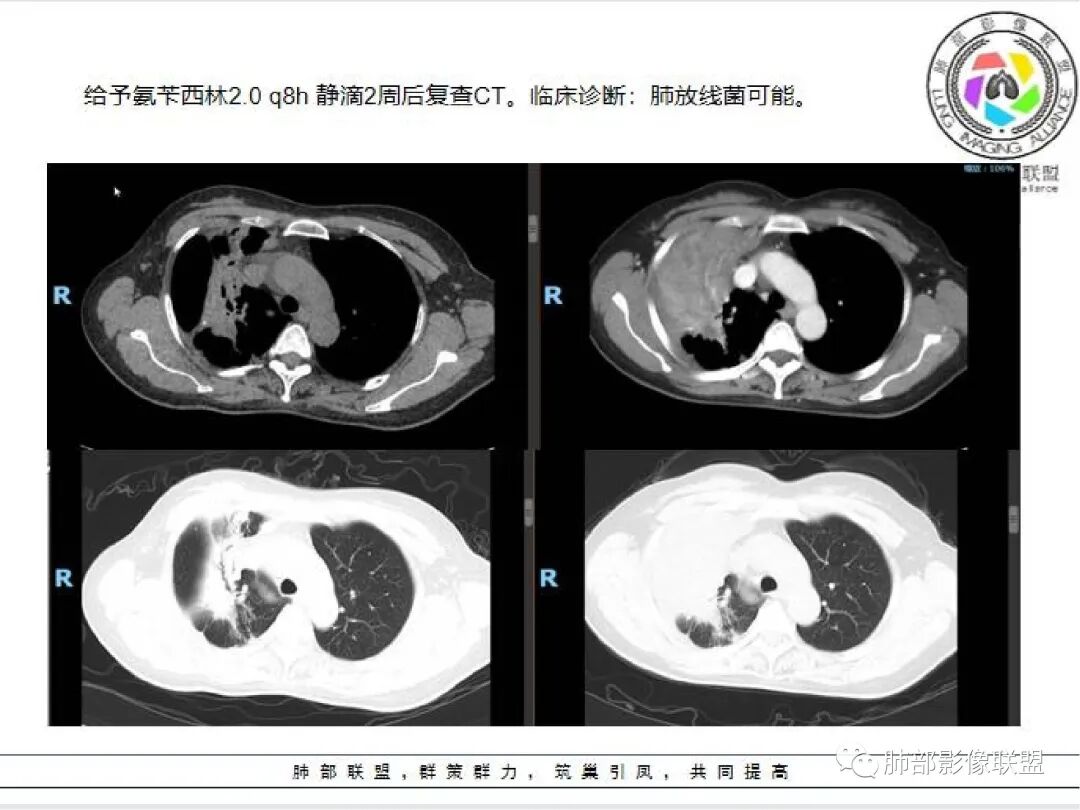

治疗前后对比CT: